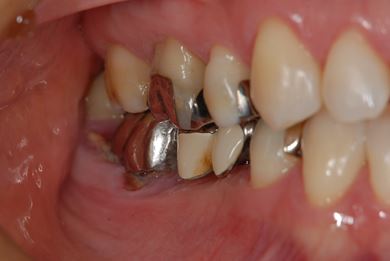

| 主訴 | ブリッジの支えとなっている歯が虫歯になり、ブリッジが難しくなったため、インプラントか義歯かの相談で来院。 | ||||||||||||||||||||||||||||||||

| 治療方針 | 抜歯と同時にインプラント治療を行い、治療期間を短縮する。 | ||||||||||||||||||||||||||||||||

| 治療内容 | インプラント4本(抜歯即日スピードインプラント治療)、ハイブリッドセラミッククラウン6本 | ||||||||||||||||||||||||||||||||